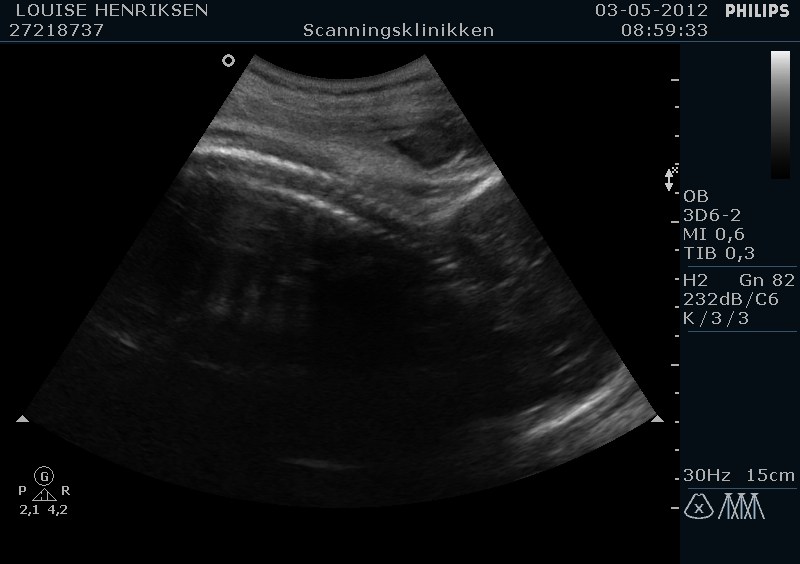

I dag skulle manden overraskes med en 4 d scanning.... og hans far var også med det var også en overraskelse, samt den lille prins....han fik bind for øjene og vi kørte mod scanning klinikken.... vi fik nogle gode sekvenser af bettemanden.. men han fylder en del derinde nu, så billederne blev ikke voldsomt gode.. men nogle fik vi dag...jeg skulle i morgen være 32 fulde uger.. mne scanningen i dag vidste34+4 dage yiarks.... jeg skal til at være færdig med den bachelor..... han vejede efter målene 1871 gram.....

så han var en fin basse...